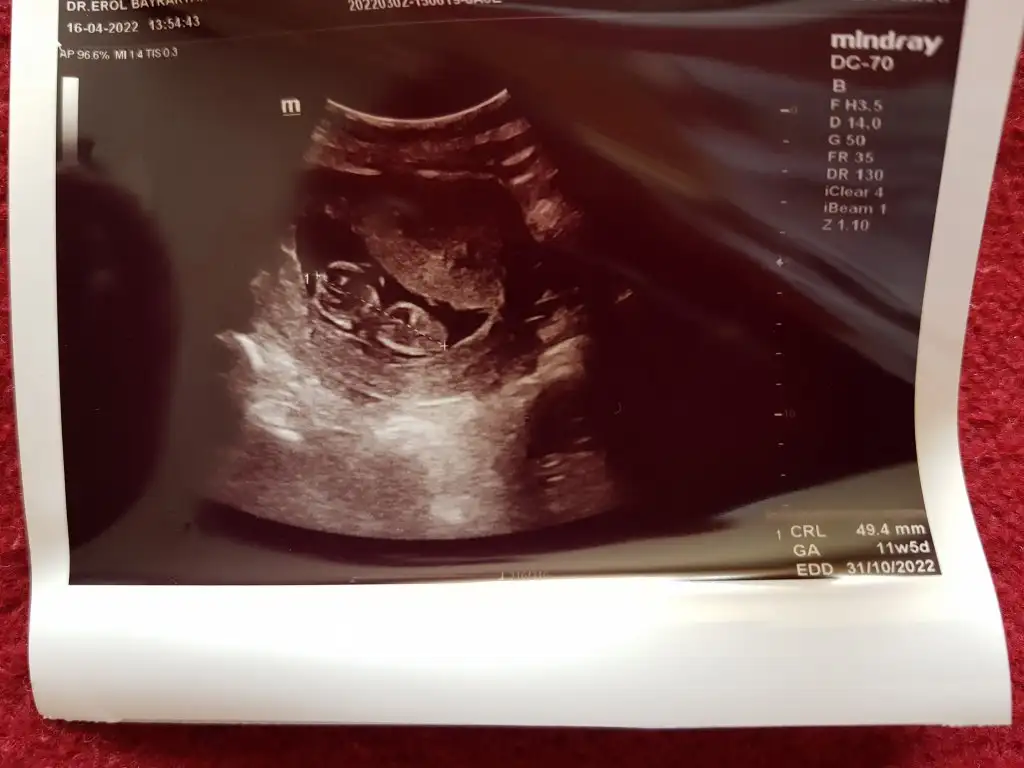

Merhaba Pasha22 Pasha22 acaba bana da yorum yapabilir misiniz? Merakla bekliyorum cinsiyeti.

Ilk foto 13+4

2.foto 11+5